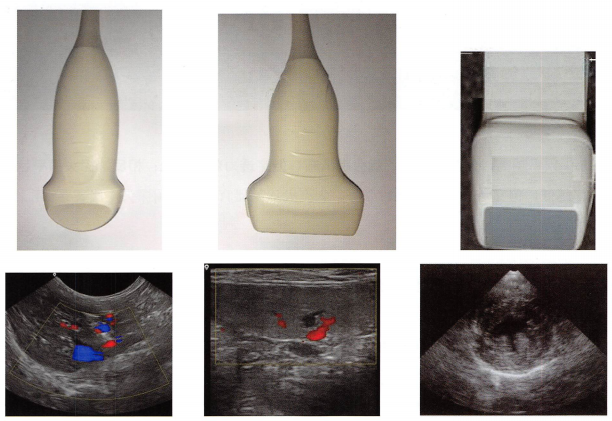

1.探头种类

小动物常用探头有微凸阵(腹部、也可以看心脏)探头声窗微凸起来可以扫查获得更大视野。线阵看浅表器官。心脏探头:声窗是平的,跟胸壁接触更好。